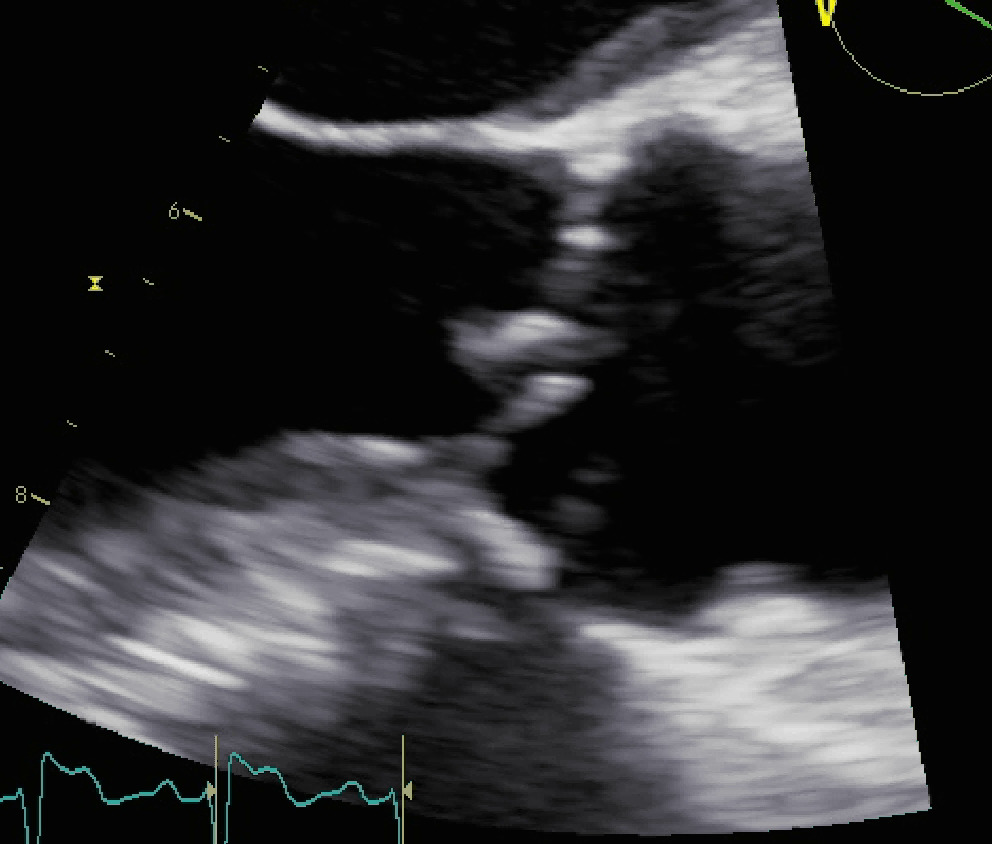

Endocardite infettiva complicata da fistola tra seno coronarico destro e ventricolo destro

Autore:

Andrea Barbieri